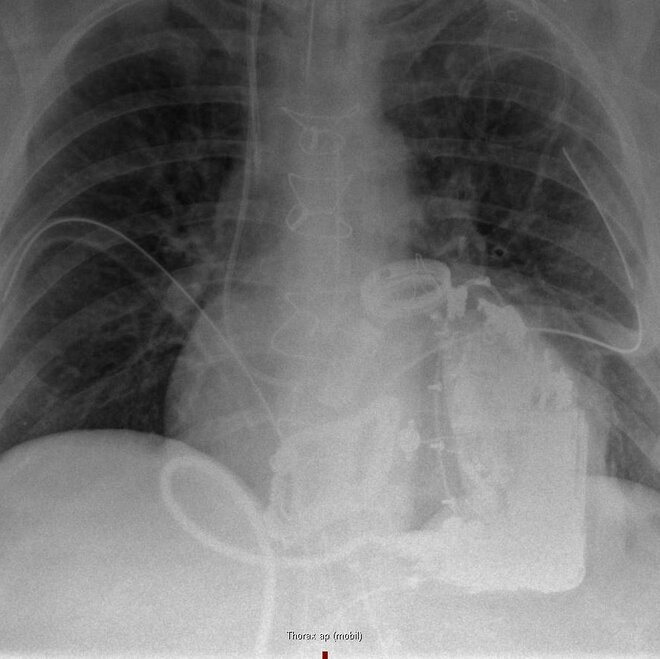

An diesem Freitag (2. August) vor genau zehn Wochen wurde einer Patientin im Klinikums Links der Weser erstmals ein Total Artificial Heart (TAH) – also ein komplett künstliches Herz implantiert. Vor einer Woche konnte die 48-Jährige Frau aus Twistringen nach Hause entlassen werden. Damit ist sie die weltweit einzige Frau, die nun in häuslicher Umgebung mit einem TAH lebt.

Ihr erkranktes Herz war Ende Mai vom Herzchirurgie-Team in einer etwa fünfstündigen Operation entnommen worden. Mit dem Aeson Carmat-Kunstherz wurde ihr das weltweit einzig zugelassene TAH implantiert. Sie war der 65. Mensch weltweit und die erste Frau, die diese moderne Kunstherzsystem bekommen hat. „Der Patientin geht es sehr gut, sie ist gut belastbar und sie fühlt sich in der Häuslichkeit sehr wohl“, berichtet Chefarzt Prof. Dr. Jens Garbade.